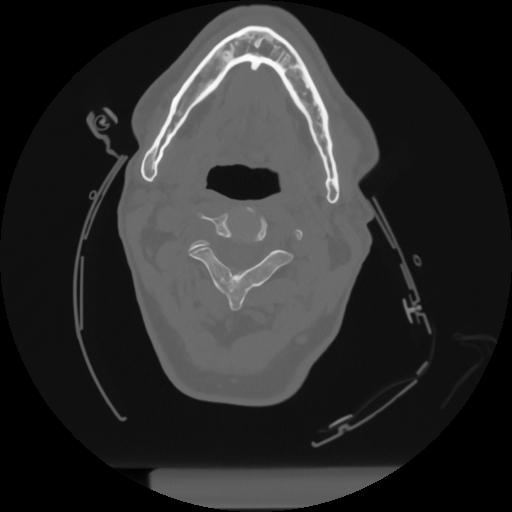

12 P.BLANDAS,,Vol,0.5,P.BLANDAS,,